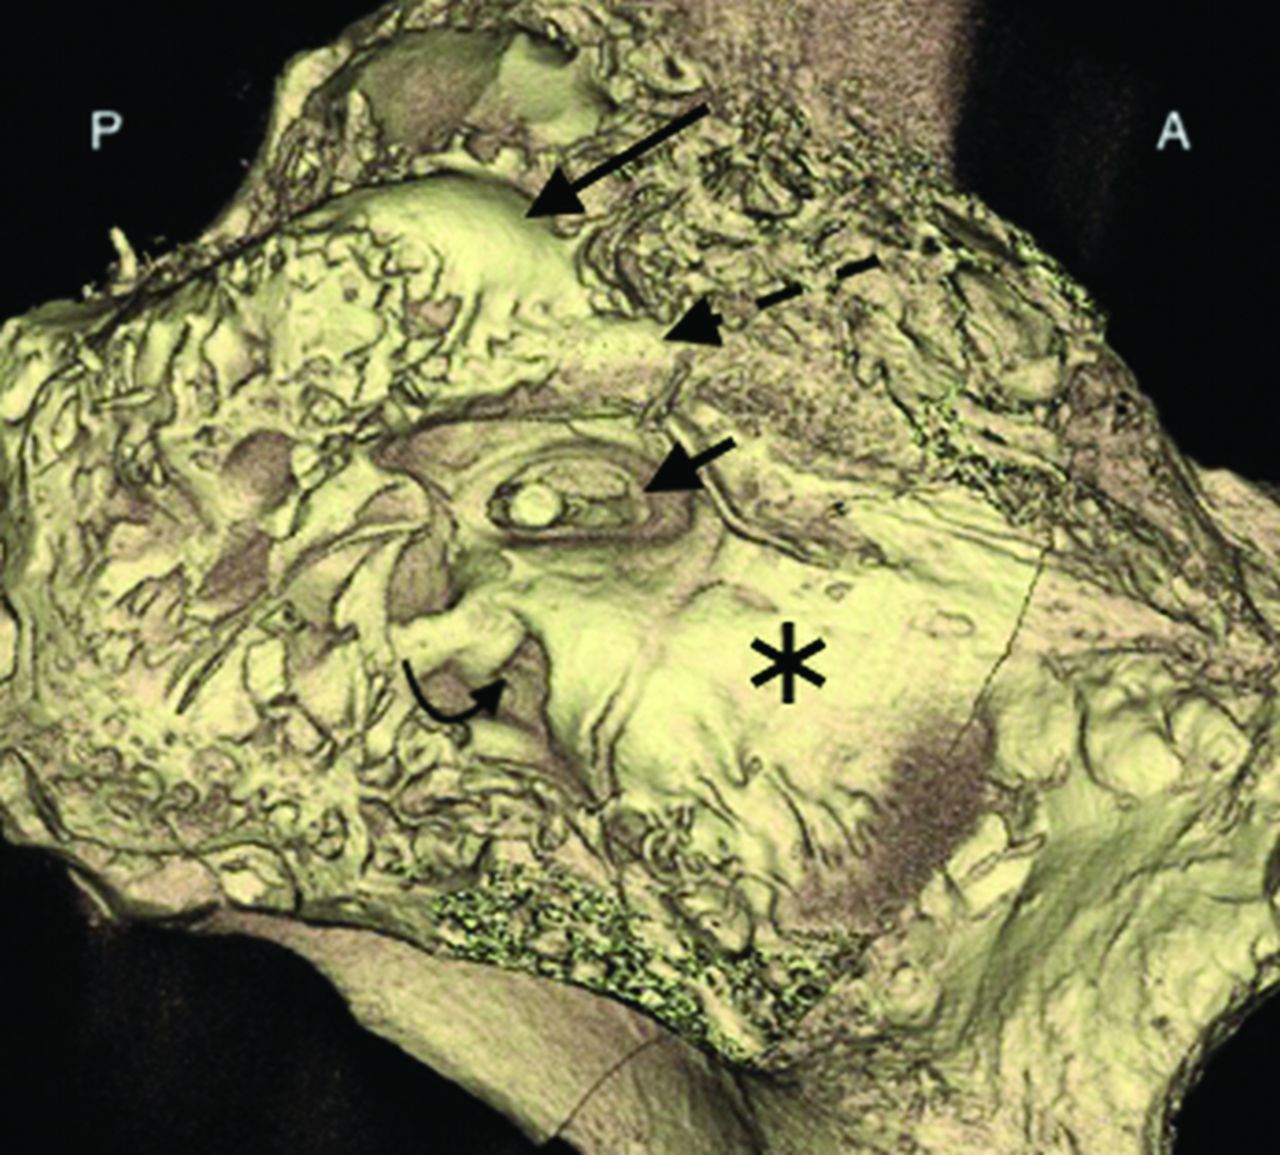

Several neoplastic processes may affect the round window membrane or round window niche. Some, such as metastases and primary osseous tumors, are centered in the bone; secondary round window involvement by these lesions depends on their size and location. Notably, most primary osteodystrophies and osseous neoplasms spare the otic capsule, given divergent embryology and composition. Other tumors have an anatomic proclivity to involve the round window membrane. For example, intralabyrinthine schwannomas may extend through the round window membrane into the niche (Fig 10).46,47 CT images of such patients may demonstrate a soft-tissue mass within the niche; visualization of the entire lesion often requires MR imaging.

Intralabyrinthine schwannoma with involvement of the round window. Axial (A and B) and coronal (C) contrast-enhanced T1WI shows an avidly enhancing mass in the left cochlea (straight arrows) and vestibule (curved arrow), compatible with a schwannoma. The mass extends through the round window membrane and into the round window niche (dashed arrows), better demonstrated on the follow-up axial (D), Pöschl (E), and coronal (F) CT images.

For cases of superior semicircular canal dehiscence, surgical plugging of the pathologic osseous defect can be completed, either via a middle cranial fossa craniotomy or transmastoid approach.55,56 Alternatively, the round window can be targeted; surgeons may reinforce the round window with overlying tissue (eg, fascia, cartilage, fat) or occlude the round window niche (Fig 12).55,57⇓⇓-60 Currently, most authors favor the former approach over the latter; although round window occlusion is considered low-risk, this strategy may induce conductive hearing loss. Furthermore, the theoretic physiologic justification for this approach is lacking because occlusion of the round window should theoretically create preferential shunting toward the pathologic third window.20,61,62

Postoperative changes of round window niche occlusion for superior semicircular canal dehiscence. Axial (A), Pöschl (B and C), and coronal (D) images of the right temporal bone demonstrate a soft-tissue opacity corresponding to a mixed temporalis fascia and irradiated rib cartilage against the round window and within the adjacent niche (straight arrow). There is frank dehiscence of the superior semicircular canal (curved arrow).

Regardless of the cochlear entry point, complications do occur. The electrode can kink, flip over at its tip, or migrate.68,69 Postoperative imaging can also demonstrate various degrees of electrode displacement, including within the semicircular canal, internal carotid artery, internal auditory canal, and vestibule.69,70 Across time, electrodes may also migrate from their initial position (Fig 13). Postoperative images should be evaluated in the context of the surgical approach (ie, via the round window or adjacent cochleostomy) and should include an assessment of electrode position, integrity, and change since prior examinations.

A 64-year-old woman who had poor progress of hearing following the placement of a cochlear implant. Axial CT image at the time of presentation (A) shows that the electrode array is retracted from its expected location, with multiple electrode leads located outside of the cochlea (straight white arrow). Follow-up imaging after surgical revision (B) shows normal positioning of the implant, with the first electrode located approximately 4 mm past the round window (curved black arrow).